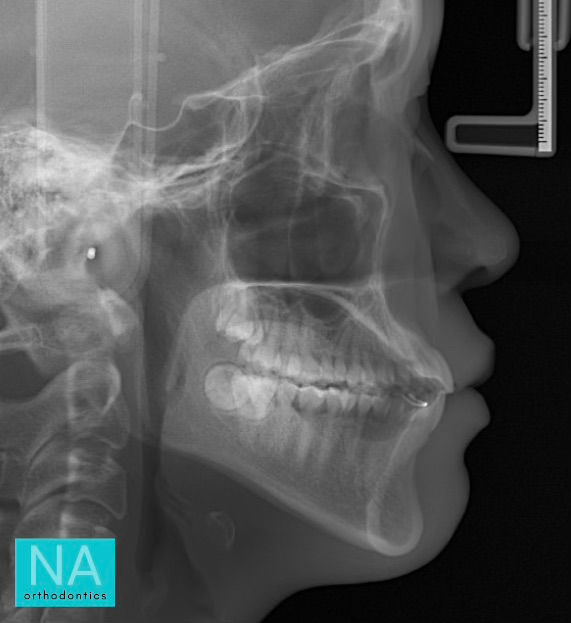

Profile before Invisalign

Before Invisalign at NA Orthodontics, patient was not happy with her profile. She felt she was too protruded and had to force her lips closed at rest.